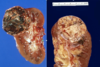

Name this tumor.

Oncocytoma - make up LESS THAN 10% of renal tumors

Comes from the INTERCHELATED CELLS of the collecting duct, males are typically affected

Mutations in chromosome 1, 14, and Y are common

KEY FEATURES:

• Tumor is well circumscribed with a CENTRAL SCAR

Tumor may appear on CT as shown here

What is shown here?

• key features?

Oncocytoma

Key Features:

- Oncocytic = pink and grainy with sheets of pink and grainy PINK cells

- UNIFORM, not much pleomorphism

- smooth cell borders